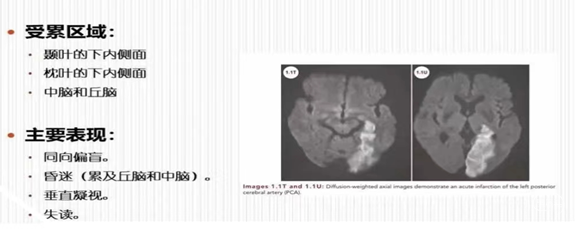

大脑后动脉梗死示意图